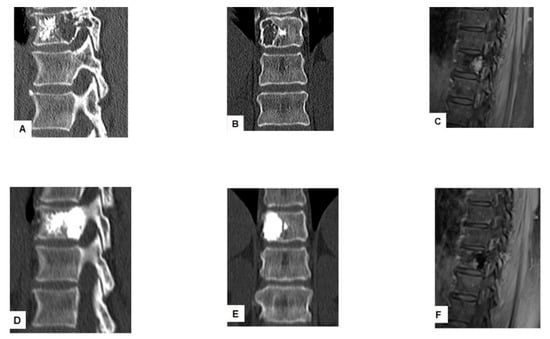

Figure 3. Successful treatment with tRFA and vertebroplasty with VA of a painful vertebral metastasis in a 74-year-old man with metastatic colon cancer. The lesion located in the posterior vertebral wall of T10 was initially treated with vertebroplasty (A,B). MRI scan T1 fat suppression shows progression of the lesion after vertebroplasty (C). tRFA was performed in the posterior vertebral body: axial and coronal CT scan reconstruction after tRFA followed by vertebroplasty (D,E). Postprocedural MRI scan T1 fat suppression after tRFA and vertebroplasty showed lack of contrast enhancement of the lesion (F).